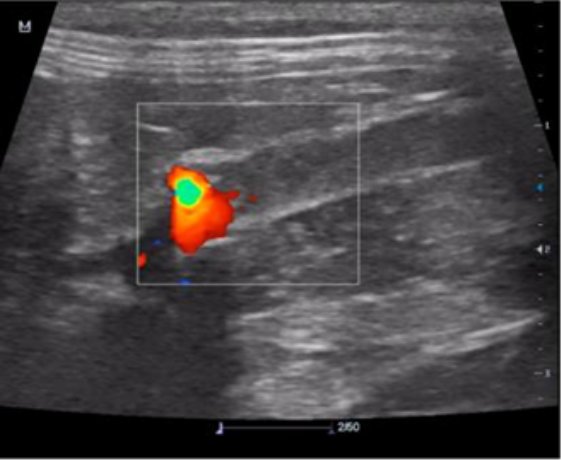

УЗИ-скрининг брюшной полости для определения границ аортального поток. Аортальный кровоток можно визуализировать с помощью цветового доплера. Аорта визуализируется дорсальнее мочевого пузыря (рис. 6).